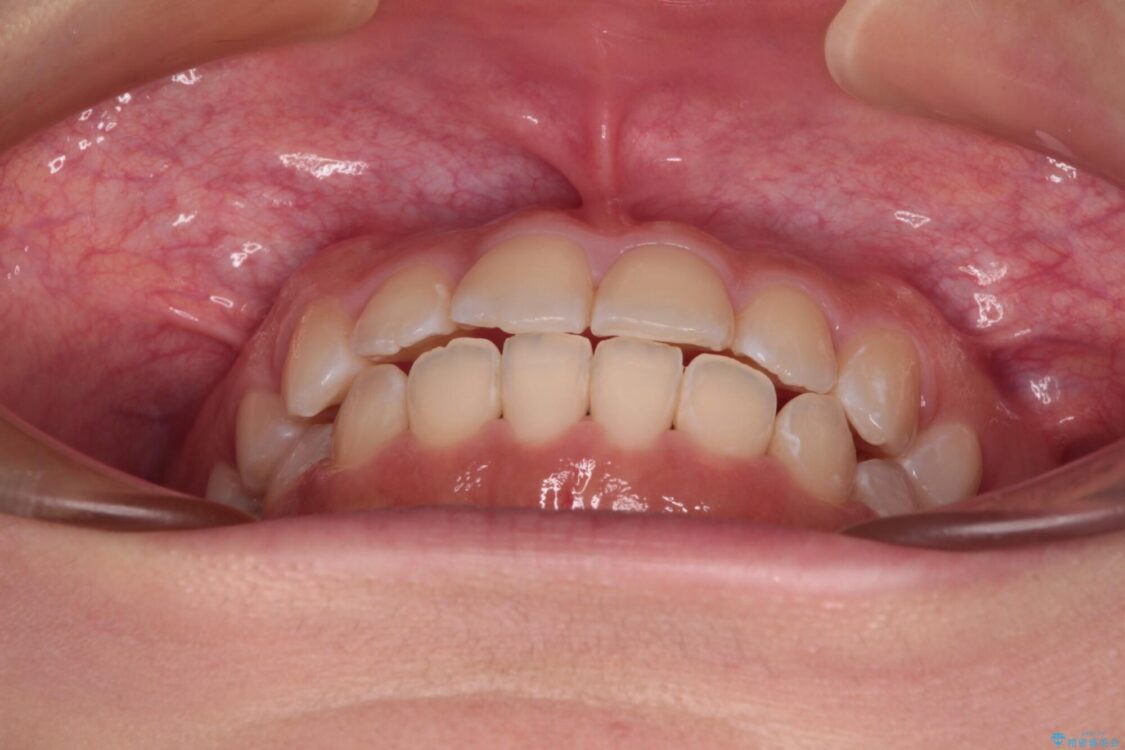

前歯のデコボコを気にして来院された患者様です。

治療前

• 【モニター】短期間で終わりたい ワイヤー装置での非抜歯矯正 治療前画像